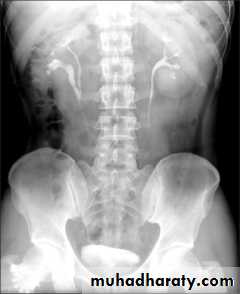

Renal agenesis :

- incidental finding.

- The opposite kidney shows compensatory hypertrophy.

- Can be diagnosed as absent kidney on ultrasound or CT.

- IVU will show a single kidney with active contrast excretion .